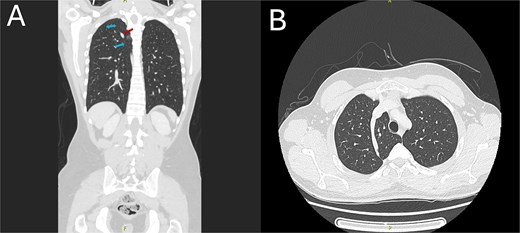

As part of the trauma protocol, a supine chest X-ray (CXR) was obtained. The trauma team suspected a pneumothorax based on the imaging showing a longitudinal lucency along the right apical area (Fig. 1). A minor right apical pneumothorax or, less commonly, a radiopaque foreign body artifact was initially suspected during radiographic assessment. A contrast-enhanced CT scan of the chest was promptly acquired due to the high-risk mechanism and the possibility of concealed thoracic injury.

Chest X-ray showing a white line crossing from the lateral to the medial side of the right upper lung. The blue arrows indicate the azygos fissure, while the red arrow points to the azygos vein located at the base of the fissure with the characteristic ``tear drop'' sign.

The azygos vein invaginates across the right upper lung during embryonic development, forming the azygos fissure, a four-layered pleural reflection that gives rise to the azygos lobe. This fissure has a distinctive inferomedial trajectory toward the right tracheobronchial angle and manifests as a thin, curvilinear opacity on CXR [3, 4]. This feature was first misidentified as a pneumothorax in our patient (Fig. 1). Previous investigations have reported similar diagnostic errors, where the appearance of the azygos lobe has been misinterpreted as other pulmonary conditions [3].